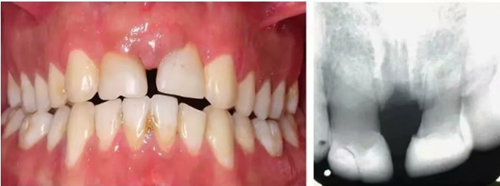

6個(gè)月后,移植牙的根尖片顯示治療期間沒(méi)有出現(xiàn)牙根吸收的影像。患者沒(méi)有出現(xiàn)不適,沒(méi)有發(fā)生牙齦炎。在23個(gè)月期間沒(méi)有進(jìn)行任何修復(fù)完成治療,達(dá)到I類關(guān)系(圖5和圖6)。

圖5. 正畸后影像學(xué)檢查

圖6. 正畸后口內(nèi)照